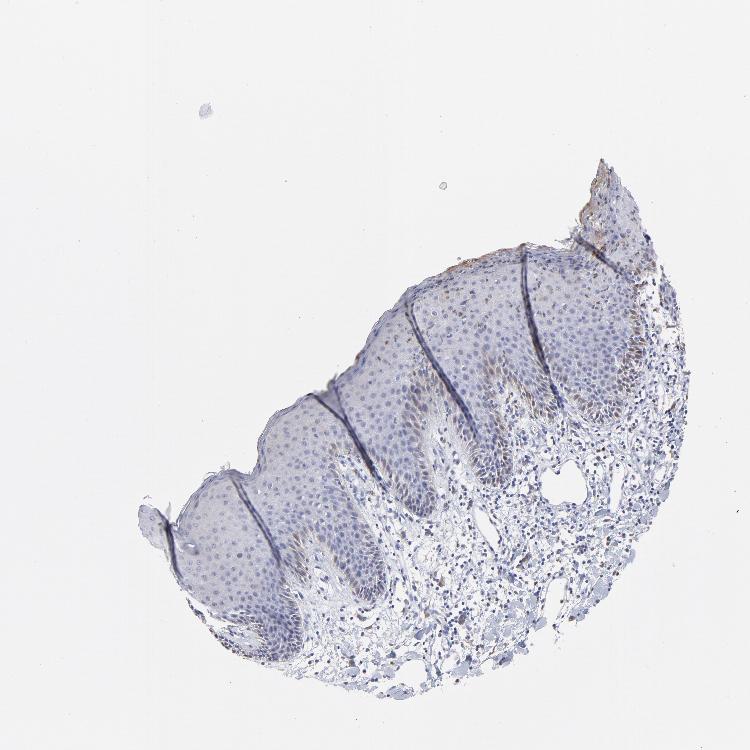

SKIN 1 - Antibody stainingi

Antibody staining in the annotated cell types in the current human tissue is reported as not detected, low, medium, or high, based on conventional immunohistochemistry profiling in selected tissues. This score is based on the combination of the staining intensity and fraction of stained cells.

Each image is clickable and will lead to virtual microscopy that enables deeper exploration of all samples and also displays staining intensity scores, fraction scores and subcellular localization as well as patient and tissue information for each sample.

Antibody HPA003335

Langerhans Not detected

Fibroblasts Not detected

Keratinocytes Not detected

Melanocytes Not detected

SKIN 2 - Antibody stainingi

Epidermal cells Low